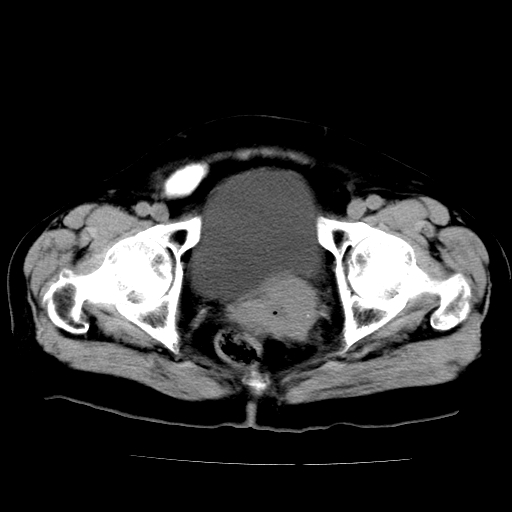

女,73岁,阴道流血一周。

宫颈不规则增大;结合临床考虑宫颈癌。建议作mri检查

1\\老年妇女突发阴道流血,常见病考虑宫颈癌.本病例宫颈部显示形态不规则,密度欠均匀,支持考虑宫 颈癌,建议mri 或阴道超声坚持

2\\但是盆腔两侧尚未见到明显肿大淋巴结等转移征象

宫颈不规则增大,左后方可见结节状突起.支持宫颈癌.

宫颈壁明显增厚,左侧为甚,宫颈癌待排,建议宫颈涂片细胞学检查。

宫颈不规则增大,周围脂肪间隙毛糙,结合临床考虑宫颈癌,盆腔内未见肿大淋巴结。